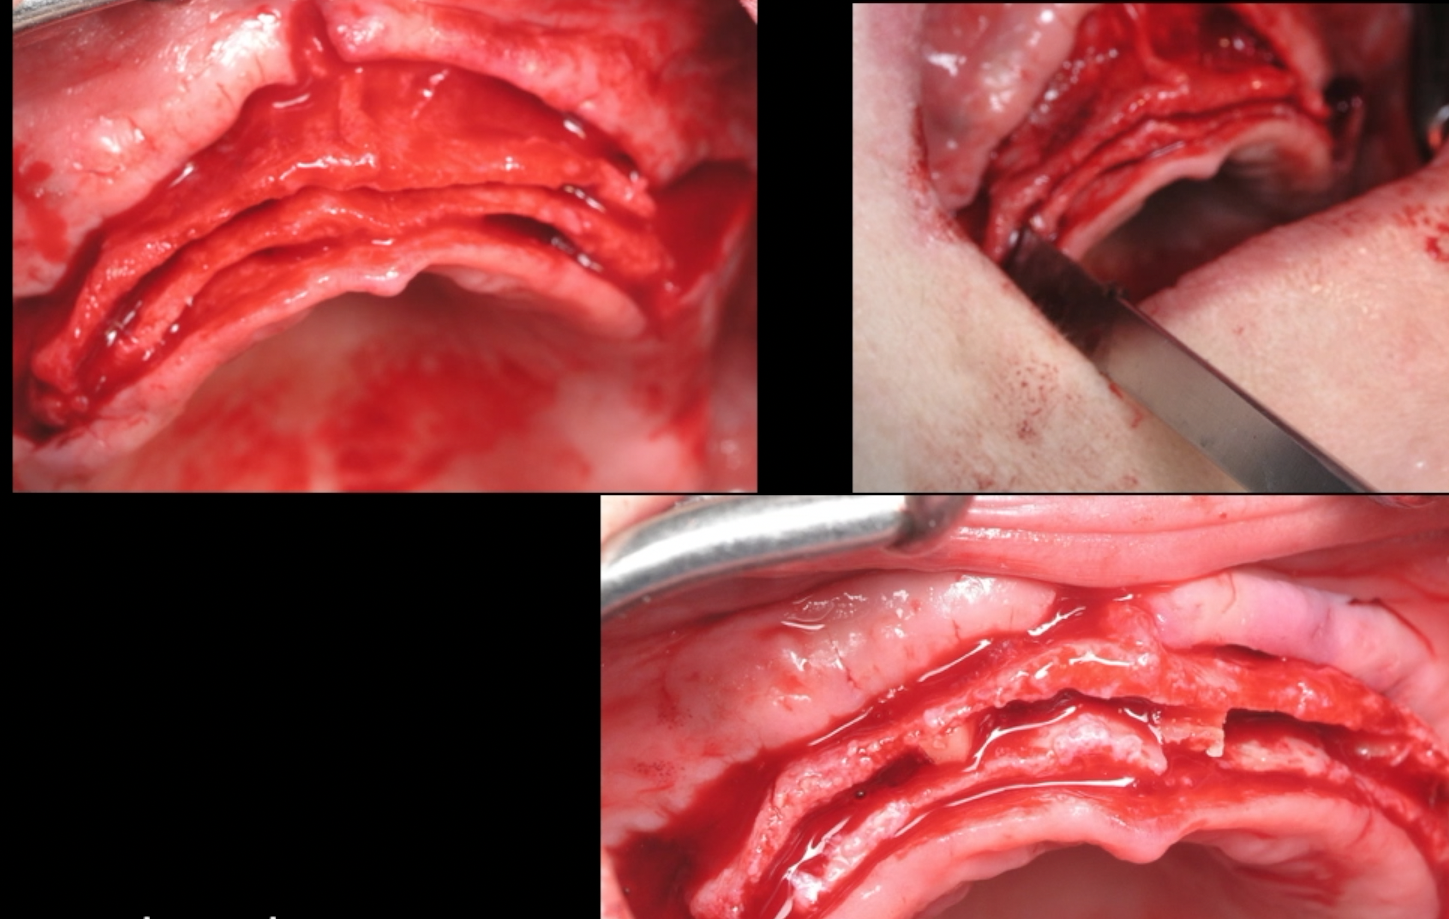

The management of the anterior open bite may be quite challenging and in some cases necessitates a multidisciplinary approach. We present here a patient suffering from an anterior open bite with an ankylosed central incisor due to previous trauma. The anterior open bite was corrected using conventional orthodontics and the ankylosed incisor was repositioned in the correct tri dimensional position using segmental osteotomy. The repositioned bone block needed 5 months of stabilization and the prosthetic rehabilitation of the anterior maxilla was completed using e-max crowns. At 24 months ,the result was stable with no relapse and an excellent pink and white esthetic score.